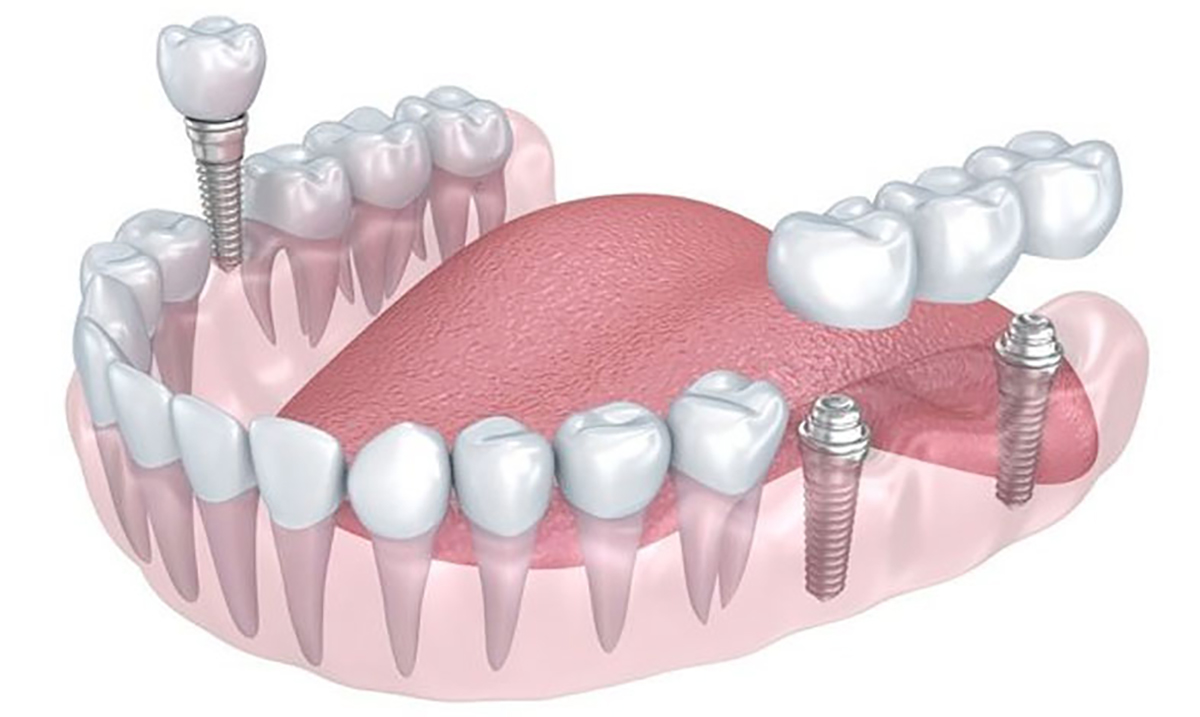

2. Implanturi dentare

Implantul dentar este o piesă din titan pur, având, în general, forma de șurub. El are menirea de a crea o rădăcină artificială în osul maxilar, acolo unde dintele sau dinții naturali lipsesc. Reconstrucția este formată din două segmente — unul intra-osos (implantul) și unul supra-osos numit bont protetic. Deasupra bontului protetic se ancorează o coroană, o punte sau o proteză. Tratamentul este conservator în comparație cu o lucrare tradițională prin punte, deoarece implanturile dentare elimină necesitatea sacrificării dinților învecinați. În cazul în care confecționăm o punte dentară, aceasta are nevoie pentru ancorare de minimum 2 dinți stâlpi, dinți ce vor fi din păcate sacrificați (se extrag nervii, se obturează canalele și se șlefuiesc dinții care odinioară erau sănătoși).

Procedura de implantare este formată din mai multe etape:

- Consultație și diagnostic 3D pentru evaluarea volumului osos;

- Etapa chirurgicală – inserarea implantului;

- Perioada de osteointegrare – 6 luni;

- Etapa protetică – fixarea coroanei definitive sau a punții pe implante.